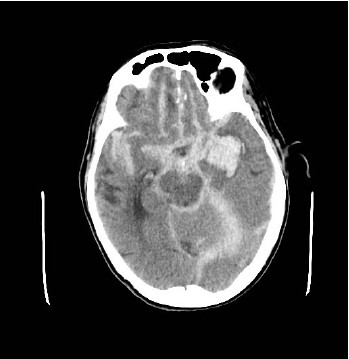

Paciente feminina, 55 anos de idade, tabagista há 25 anos com carga de 10 maços ano. Deu entrada no Grande Trauma com Glasgow 6, trazida pelo SAMU com relato de ter sido encontrada desacordada em casa pela vizinha. Realizada TC Crâneo (imagem 1):

Segundo o diagnóstico pela TC de Crâneo, as medidas a seguir fazem parte da prevenção da lesão neurológica secundária, exceto:

Ainda relativo à TAC de crânio do caso anterior, qual descrição abaixo caracteriza melhor a imagem no contexto do caso: